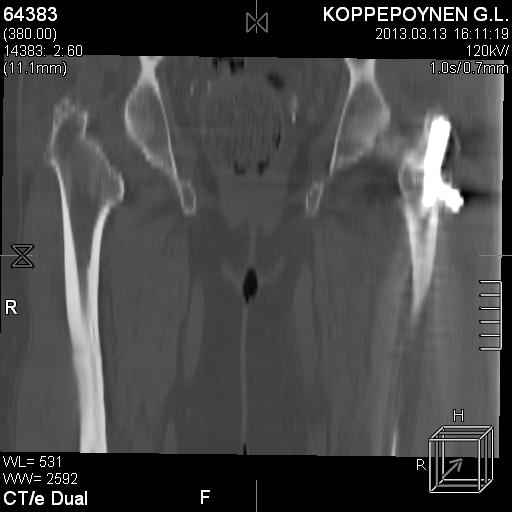

[Ortho] Чрезподвертельный перелом бедра. Остеосинтез стержнем. Перелом металлофиксатора. Дальнейшая тактика?

Делали КТ после операции.